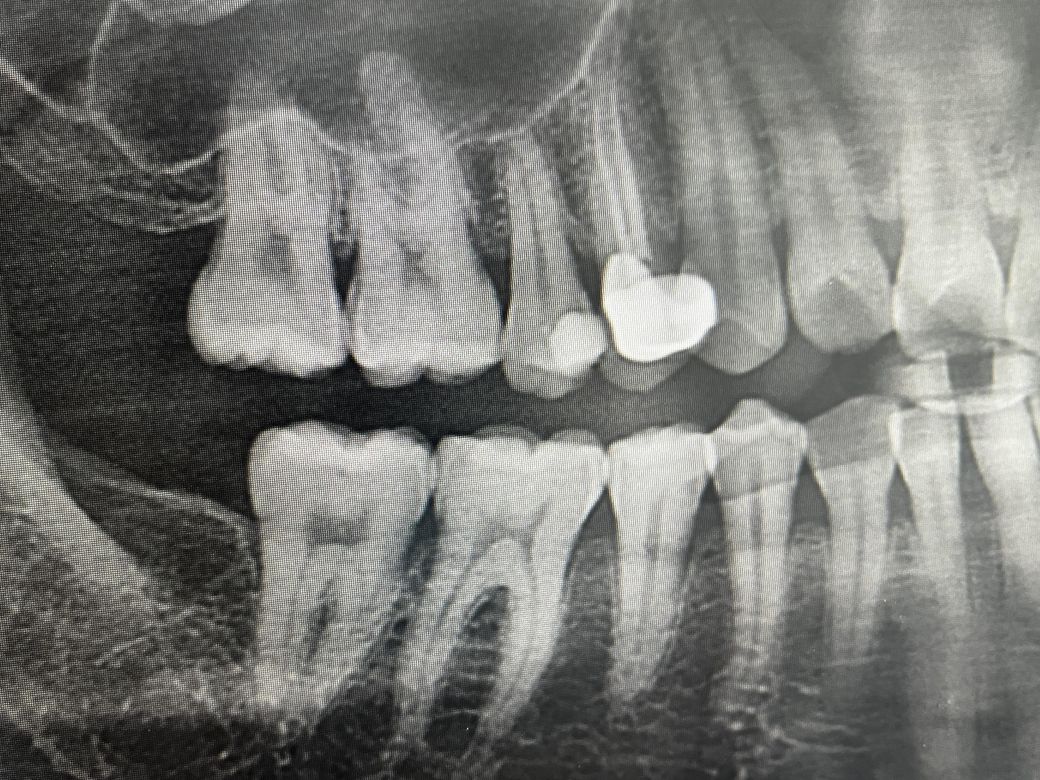

충치 치료에 대한 방향성이 고민입니다

15번인데 현재 gi로 채웠습니다

신경치료를 해야할까요?

만약 신경치료를 한다면 포스트가 필요할까요?

증상이 있으시면 신경치료 하시면 되고 아니면 인레이 하시면 됩니다. 사진 상 포스트는 꼭 필요해보이지는 않습니다.

화질이 선명하지 않아 영상으로는 정확한 결정을 내리기 어려우며 신경치료 여부는

전기 치수 생활력 검사, 와동검사,

타진 반응, 교합 테스트, 냉반응 등 여러 가지를 종합해서 판단해야 합니다.

신경치료를 하면 통증과 심림증은 없어질 수 있으나 치아의 수명이 짧아지는 단점이 있습니다.

해당 치아를 신경치료로 할 경우 포스트까지는 하지 않아도 될 것으로 보입니다.

신경치료를 하게되면 포스트가 필요 할꺼 같습니다. 시리지 않으면 일단 인레이로 마무리 하시고 시리거나 이멕스 인레이를 하고 나서도 불편하시면 신경치료를 해야될 가능성이 있습니다.

충치가 워낙 깊기 때문에 신경치료의 필요성을 배제할 순 없겠습니다만 현재 증상이 괜찮다면 굳이 신경치료를 서둘러 할 필요까지는 없어보입니다.

치질(남은 치아의 양)이 아주 충분하진 않지만 그래도 한쪽면을 제외하고 나머지는 건전한 치질이므로 굳이 포스트까지는 하지 않아도 괜찮을 것 같습니다.

포스트는 지하에 4분의 3 정도가 없어졌을 경우에 하는 경우가 많습니다.

사진으로만 봤을 경우에는 포스트가 필요하지 않을 것으로 보이나 충치를 추가적으로 제거하고 난 다음에 치아에 머리 부분이 너무 작다면 포스트를 해야 하는 경우도 생길 수 있습니다.